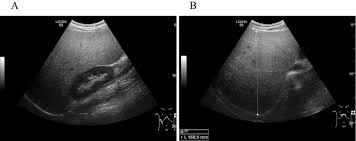

Echinococcal Cyst